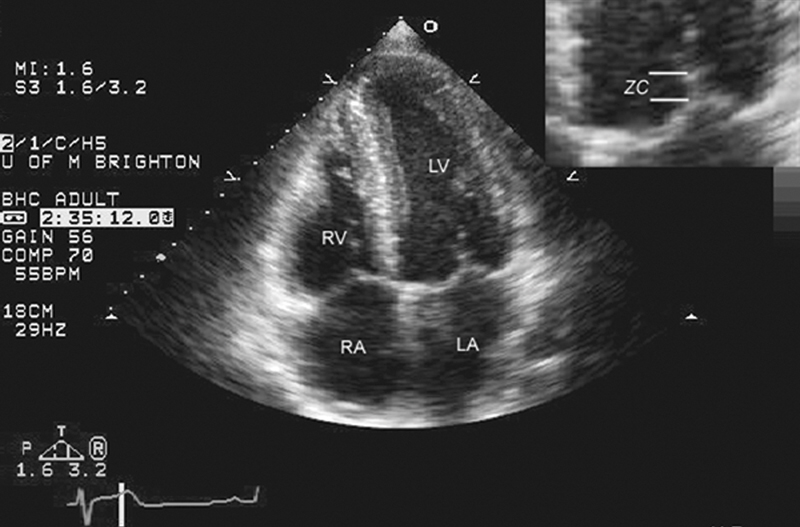

فحوصات تشخيصية لبعض امراض القلب والشرايين التاجية